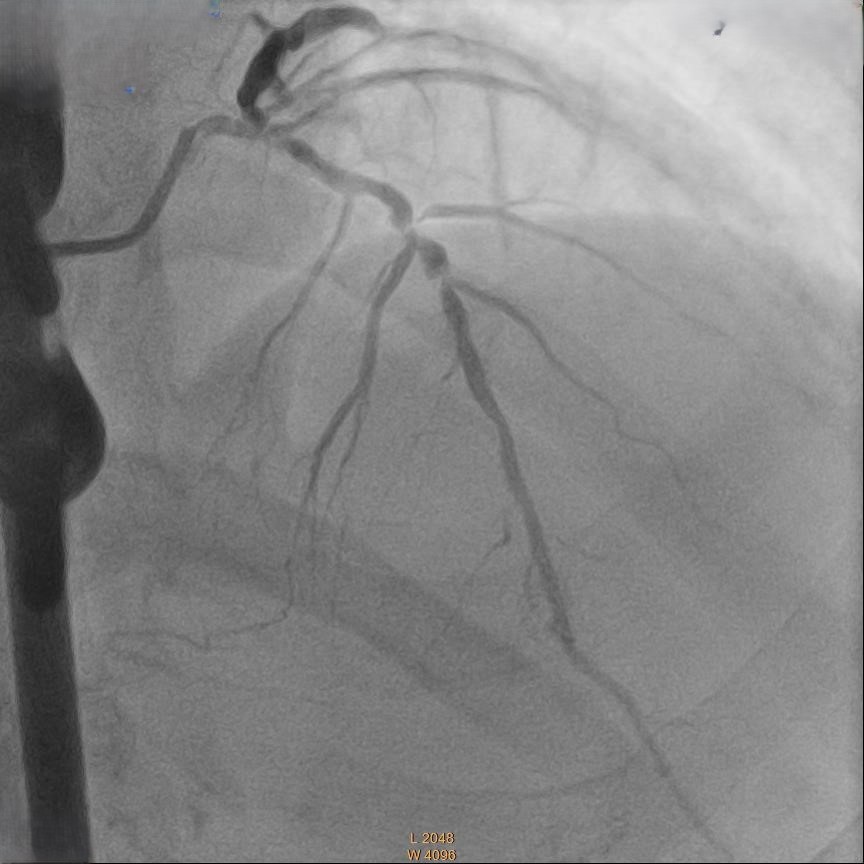

Relevant Catheterization Findings

Coronary angiography showed 50% stenosis at Left Main (LM), proximal to mid Left Anterior Descending Artery (LAD) 70% stenosis, 80% stenosis at mid Left Circumflex Artery (LCX) and Chronic Total Occlusion at mid Right Coronary Artery (RCA) with collateral from LAD.

Right femoral artery punctured approach by 7Fr femoral sheath. Coronary guide catheter EBU 3.5 was used to engage left coronary artery. Percutaneous Coronary Intervention (PCI) to bifurcation Medina 1,1,1 using T and small protrusion (TAP) technique. LAD and LCX wired with workhorse wire . Mid LAD predilated with Semi-compliant (SC)2.5mm balloon and proximal LAD predilated with non-compliance (NC) 3.5mmballoon. Intravascular Ultrasound ( IVUS) was performed to measure the vessel size, lesion length and plaque morphology. Mid LAD stented with 3.5x23 mm drug eluting stent (DES). LM until proximal LAD stented with 4x33mm DES . Proximal optimization therapy (POT) at LM with NC balloon 5x8mm. Proximal LAD post dilated with NC balloon 4x20mm and mid LAD post dilated with NC balloon 3.5x15mm. LCX rewired with workhorse wire. Ostial LCX predilated with NC balloon 3.5x15mm and stented with 3.5x23mm DES subsequently post dilated with NC balloon 3.75x20mm. Final kissing balloon inflation was done at ostial LAD using NC balloon 4.0 and ostial LCX using NC balloon 3.75. Final IVUS noted double barrel sign at LM stent and confirmed with stent enhancement likely due to abluminal side branch wiring. Final POT to LM with NC balloon 5x8mm. Final IVUS showed good stent expansion and opposition with no dissection.